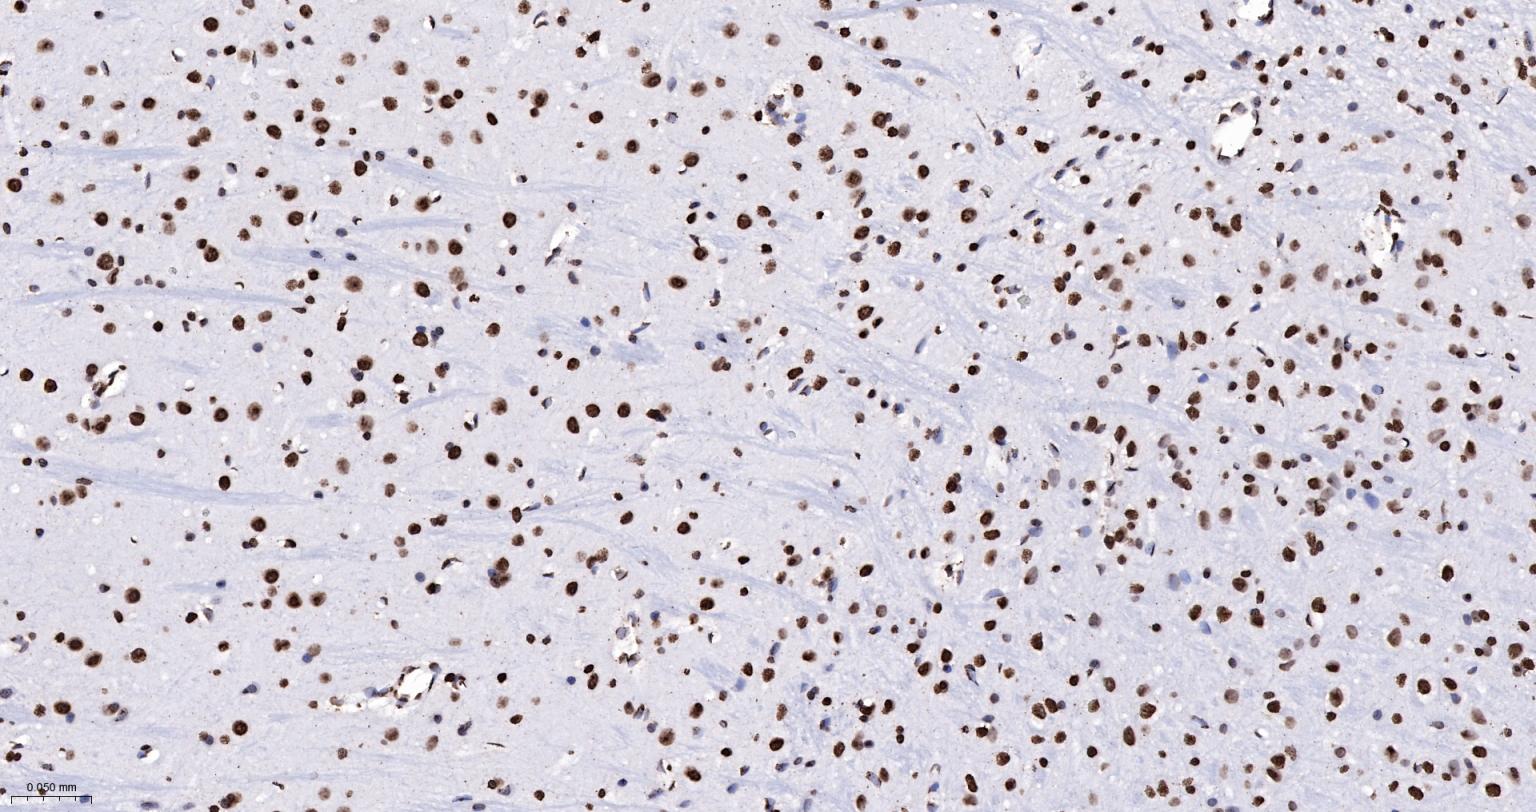

Paraformaldehyde-fixed, paraffin embedded Human Cerebrum; Antigen retrieval by boiling in sodium citrate buffer (pH6.0) for 15 min; Antibody incubation with Histone H4 Monoclonal Antibody, Unconjugated(bsm-52111R) at 1:200 overnight at 4°C, followed by conjugation to the bs-0295G-HRP and DAB (C-0010) staining.

Paraformaldehyde-fixed, paraffin embedded Rat Cerebrum; Antigen retrieval by boiling in sodium citrate buffer (pH6.0) for 15 min; Antibody incubation with Histone H4 Monoclonal Antibody, Unconjugated(bsm-52111R) at 1:200 overnight at 4°C, followed by conjugation to the bs-0295G-HRP and DAB (C-0010) staining.

Paraformaldehyde-fixed, paraffin embedded Mouse Cerebrum; Antigen retrieval by boiling in sodium citrate buffer (pH6.0) for 15 min; Antibody incubation with Histone H4 Monoclonal Antibody, Unconjugated(bsm-52111R) at 1:200 overnight at 4°C, followed by conjugation to the bs-0295G-HRP and DAB (C-0010) staining.